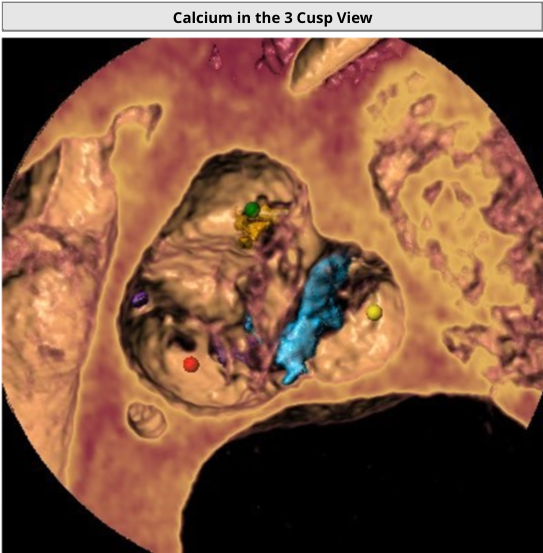

Calcification distribution

3 Cusp View:LAO11° CAU7°

瓣叶增厚伴钙化,术前超声显示赘生物漂浮

瓣叶增厚冗长,但双侧冠脉开口高度尚可,并使用上端支架梁少,大开口Acurate neo2主动脉瓣膜,避免冠脉遮挡

Sentinel脑保护下进行手术,预防赘生物脱落,造成卒中